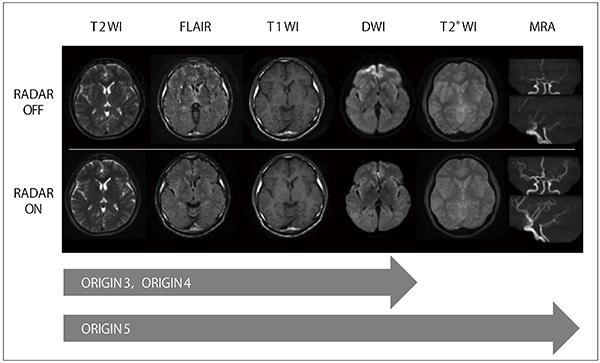

また,システムソフトウエアがVer3以上の高磁場MRI装置であれば,ブレードを形成したRADARにパラレルイメージングのRAPIDを併用できます(図2c)。ORIGIN5ではRADARがGE法や3D-TOF-MRAにも使用できるようになり(図3),最新のORIGIN6以降では静音シーケンスとの併用も可能となります。そのほか,BASGシーケンスでもRADARが可能であり,これらすべてのシーケンスにおいてコイルの制限やスライス断面の制限を設けておらず,同期計測の併用も可能なため,全身で使用できます。

図3 RADAR適応シーケンスと画像